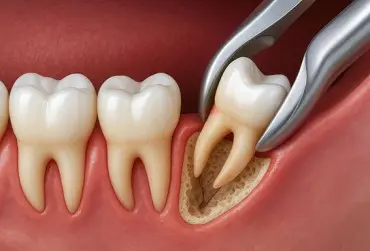

Ból po ekstrakcji zęba jest jednym z najczęstszych powikłań w praktyce stomatologicznej i stanowi istotny problem z perspektywy zarówno pacjenta, jak i lekarza. Jest on efektem urazu chirurgicznego obejmującego tkanki miękkie, tkanki kostne i ozębną, co prowadzi do aktywacji reakcji zapalnej oraz uwalniania mediatorów bólu, takich jak prostaglandyny, bradykinina, histamina i cytokiny prozapalne [1]. Właściwa kontrola bólu nie jest wyłącznie kwestią komfortu. Ma także znaczenie kliniczne, gdyż ból nieleczony może prowadzić do problemów z przyjmowaniem pokarmów, zaburzeń snu, obniżenia odporności organizmu, a także powikłań gojenia, w tym zespołu suchego zębodołu [2]. Jednym z leków szczególnie przydatnych w leczeniu bólu poekstrakcyjnego jest nimesulid.